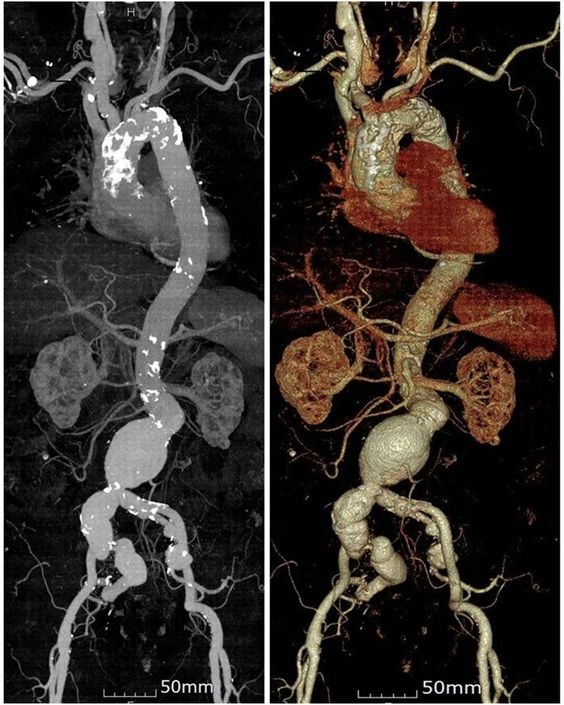

- Томограмма брюшной полости демонстрирует наличие патологических очагов в желудочно-кишечном тракте, а также забрюшинном пространстве, почках, печени, нарушения в работе лимфатическо-сосудистой системы этой области.

- Ангиография – аорты, сосудов, конечностей, шеи, головного мозга.

- Брюшной полости – печени, селезенки, желчного пузыря, поджелудочной железы, надпочечников, почек, забрюшинной области.

Чаще всего КТ используют при подозрении на онкопроцесс глубоко расположенных органов - головного мозга, органов грудной полости и средостения, брюшной полости, забрюшинного пространства, малого таза. Ввиду того, что такой альтернативный для КТ метод как МРТ недостаточно эффективен при исследовании костного аппарата, КТ при онкологии костей является единственным высокоточным методом диагностики.

Синдром портальной гипертензии встречается при множестве заболеваний: тромбозе и сдавлении портальной вены и её ветвей, застойной сердечной недостаточности, циррозе печени, опухолевом процессе, холангите и др. КТ признаки портальной гипертензии заключаются в расширении воротной вены, расширенных коллатеральных венах (особенно вокруг пищевода), наличии выпота в брюшной полости (асците) и увеличенной селезенке.

Гемангиома — наиболее часто встречающееся доброкачественное образование печени. При обычном сканировании небольшие гемангиомы выглядят как четко отграниченные округлые зоны однородно пониженной плотности. После внутривенного введения контраста возникает усиление сигнала на периферии образования, а затем постепенное распространение к центру (центрипетальный характер заполнения). В случае крупных гемангиом это может занять несколько минут и усиление может быть негомогенным.